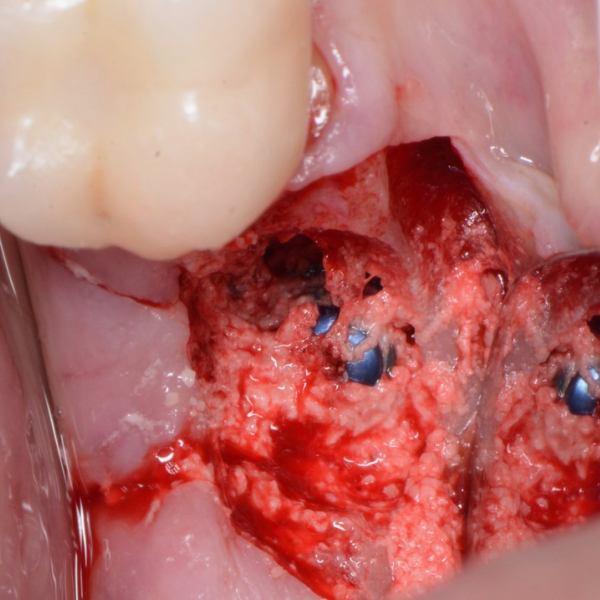

Tooth 14 slightly increased mobility, tenderness and bite pain. Suspected root fracture

Patient suffered from a root fracture. Needed removal and to restore hard and soft tissue.